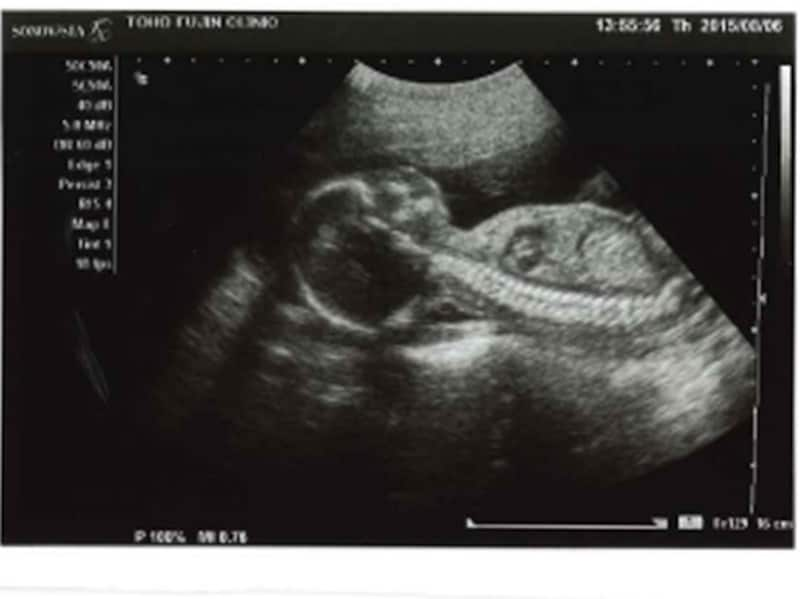

妊娠21週目エコー写真・胎動の様子・胎児の大きさや体重・性別

脳神経細胞が増えて大きくなり、脳が再び急成長を始めるため、赤ちゃんができることが増えていきます。筋肉や骨格も発達する上に、羊水の量も増えてくるので、子宮内での赤ちゃんの動きはより活発化。また、手はものをつかめるほどに成長しています。